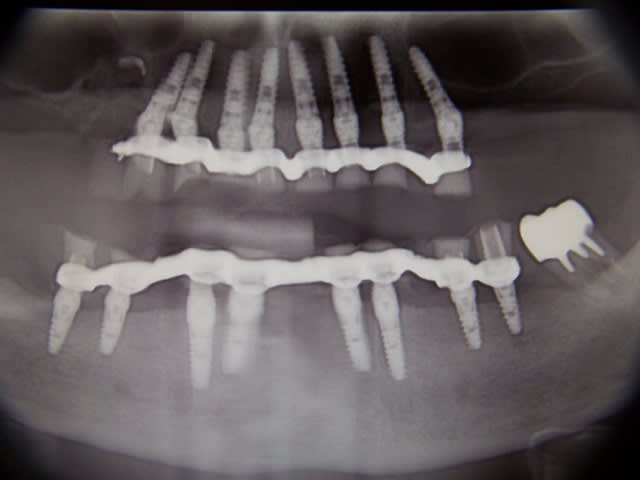

S.I.A.O

(simulation implantaire assistée par ordinateur)